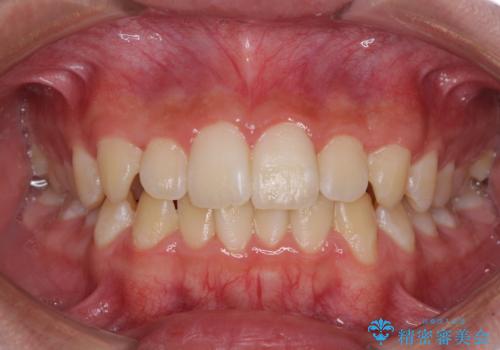

しっかり使って短期間で治療 インビザラインによる叢生解消

担当医 藤巻太一朗

軽度の前歯のガタガタをインビザラインでの目立たない矯正

八重歯・前歯のがたつき 抜かない矯正 インビザラインで